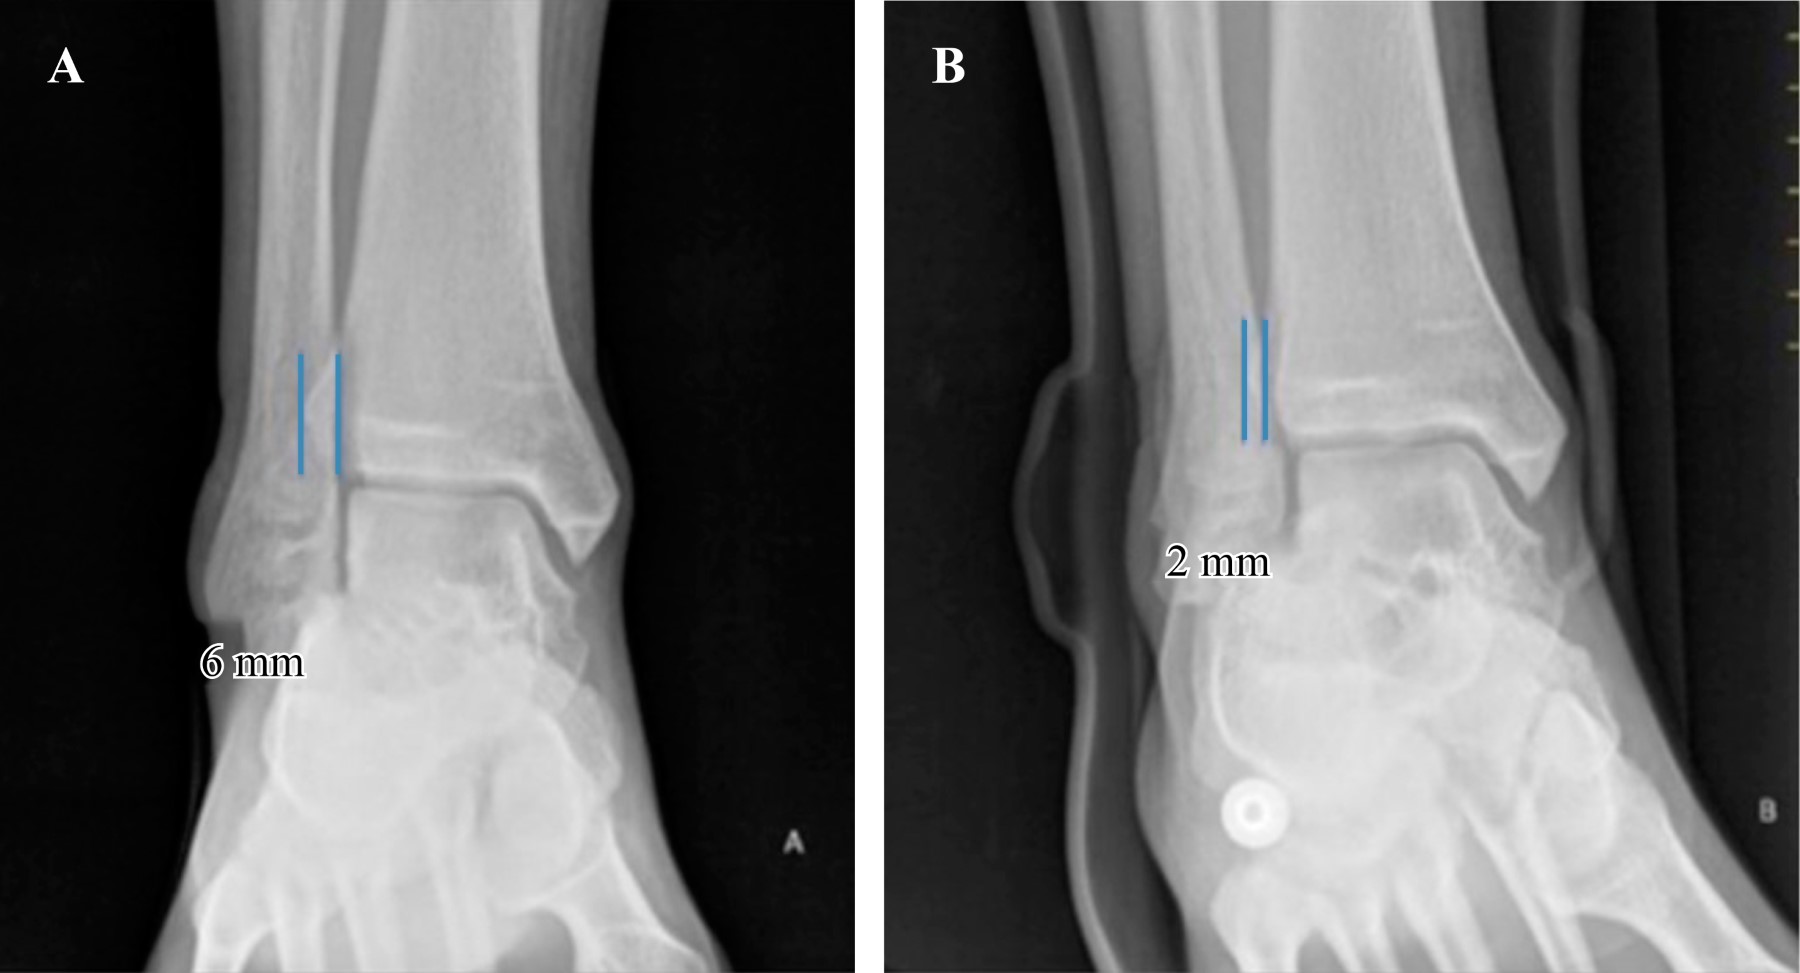

La medición del ETP se realizó a 10 mm de la superficie articular y se encontró que todos los tobillos tenían un espacio igual o menor a 6 mm: seis tobillos presentaron 6 mm (13%), 11 mostraron 5 mm (24%), 23 tuvieron 4 mm (50%) y seis presentaron 3 mm (13%) (Tabla 1).

En cuanto a las mediciones obtenidas de la STP, todas se midieron a 10 mm de la superficie articular. Se encontró que todas fueron mayores a 1 mm: nueve tobillos presentaron 1 mm (19.5%), 31 registraron 2 mm (67.4%) y solo seis tobillos tuvieron 3 mm (13%) (Tabla 1).

El EATM se midió en todas las radiografías, encontrando una constante entre 2 y 3 mm en todos los tobillos: 11 tobillos presentaron un EATM de 2 mm (24%) y los 35 restantes tuvieron 3 mm (76%) (Tabla 1).